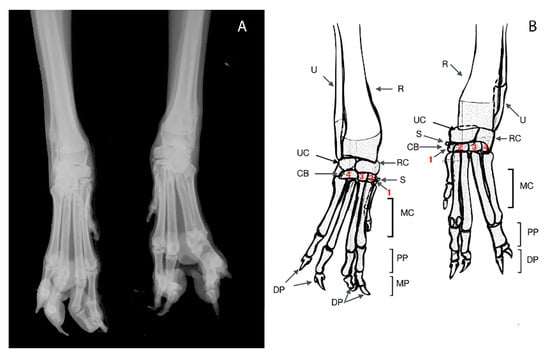

2.3. Case 1